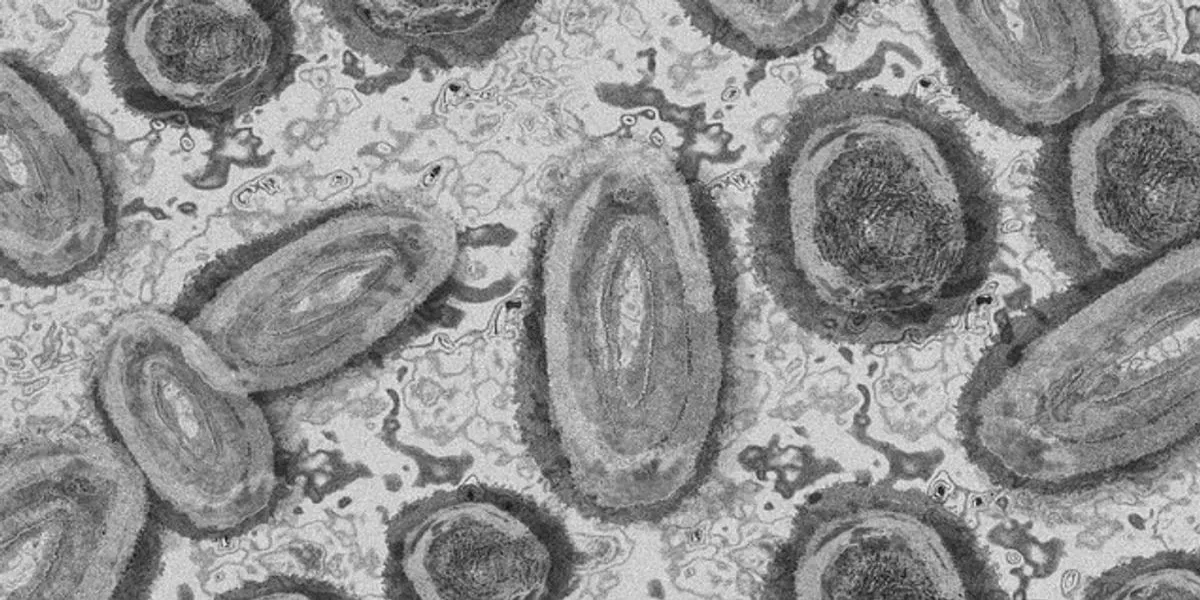

O primeiro caso da Monkeypox, conhecida como varíola dos macacos, foi confirmado nesta quarta-feira (8/6) no Brasil. Um homem de 41 anos, natural de São Paulo, foi diagnosticado com a doença depois de viajar por Espanha e Portugal. As informações foram confirmadas pelo portal Uol.

Ele está internado no Instituto de Infectologia Emílio Ribas, na capital paulista. Segundo a Secretaria de Estado de Saúde de São Paulo, o homem teve sintomas como febre e mialgia a partir de 28 de maio.

As amostras do caso ainda estão em análise pelo Instituto Adolfo Lutz, que é a referência e o Laboratório Central em Saúde Pública (Lacen), de São Paulo.

O Ministério da Saúde ainda investiga outros sete casos suspeitos da doença. Os demais são pacientes que vivem em Porto Alegre, Corumbá-MS, Blumenau-SC, Dionísio Cerqueira-SC, Rio Crespo-RO (2) e Pacatuba-CE. Cinco suspeitas são em homens e três em mulheres, e seis deles têm de 25 a 32 anos.

Os pacientes tiveram lesões na pele, febre e os linfonodos inchados.